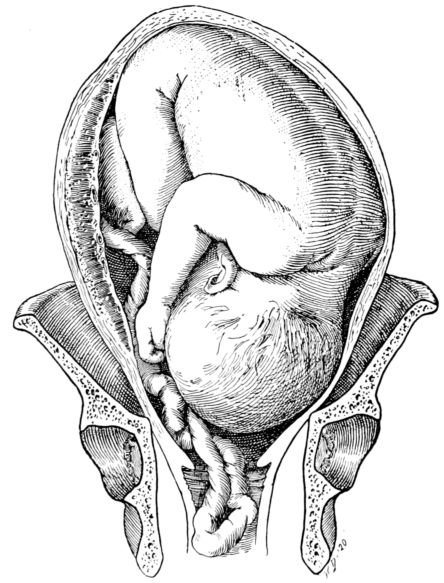

| 27. | Full term fetus in utero | 81 |

| 50. | Attitude of fetus in uterus at term | 217 |

| 52. | Attitude of fetus in breach presentation | 219 |

| 53. | Attitude of fetus in vertex presentation | 220 |